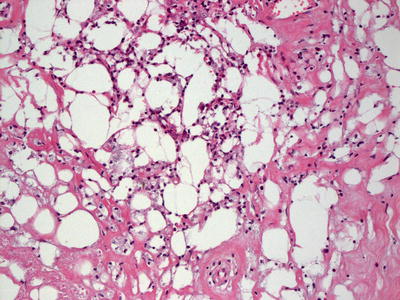

Even though the pathogenesis differs, the histologic findings in traumatic fat necrosis are identical to those described in factitial panniculitis [42, 46]. A lobular panniculitis with abundant fat necrosis and a dense mixed inflammatory infiltrate characterizes traumatic panniculitis (Figs. 9.12, 9.13 and 9.14). Rare cases develop a pseudomembrane that lends a lobulated appearance to the neutrophil-rich inflammatory infiltrate [47]. This pseudomembrane is likely a result of necrotic adipocytes.

Fig. 9.12

Traumatic fat necrosis causes a lobular and septal panniculitis with no anatomic boundaries